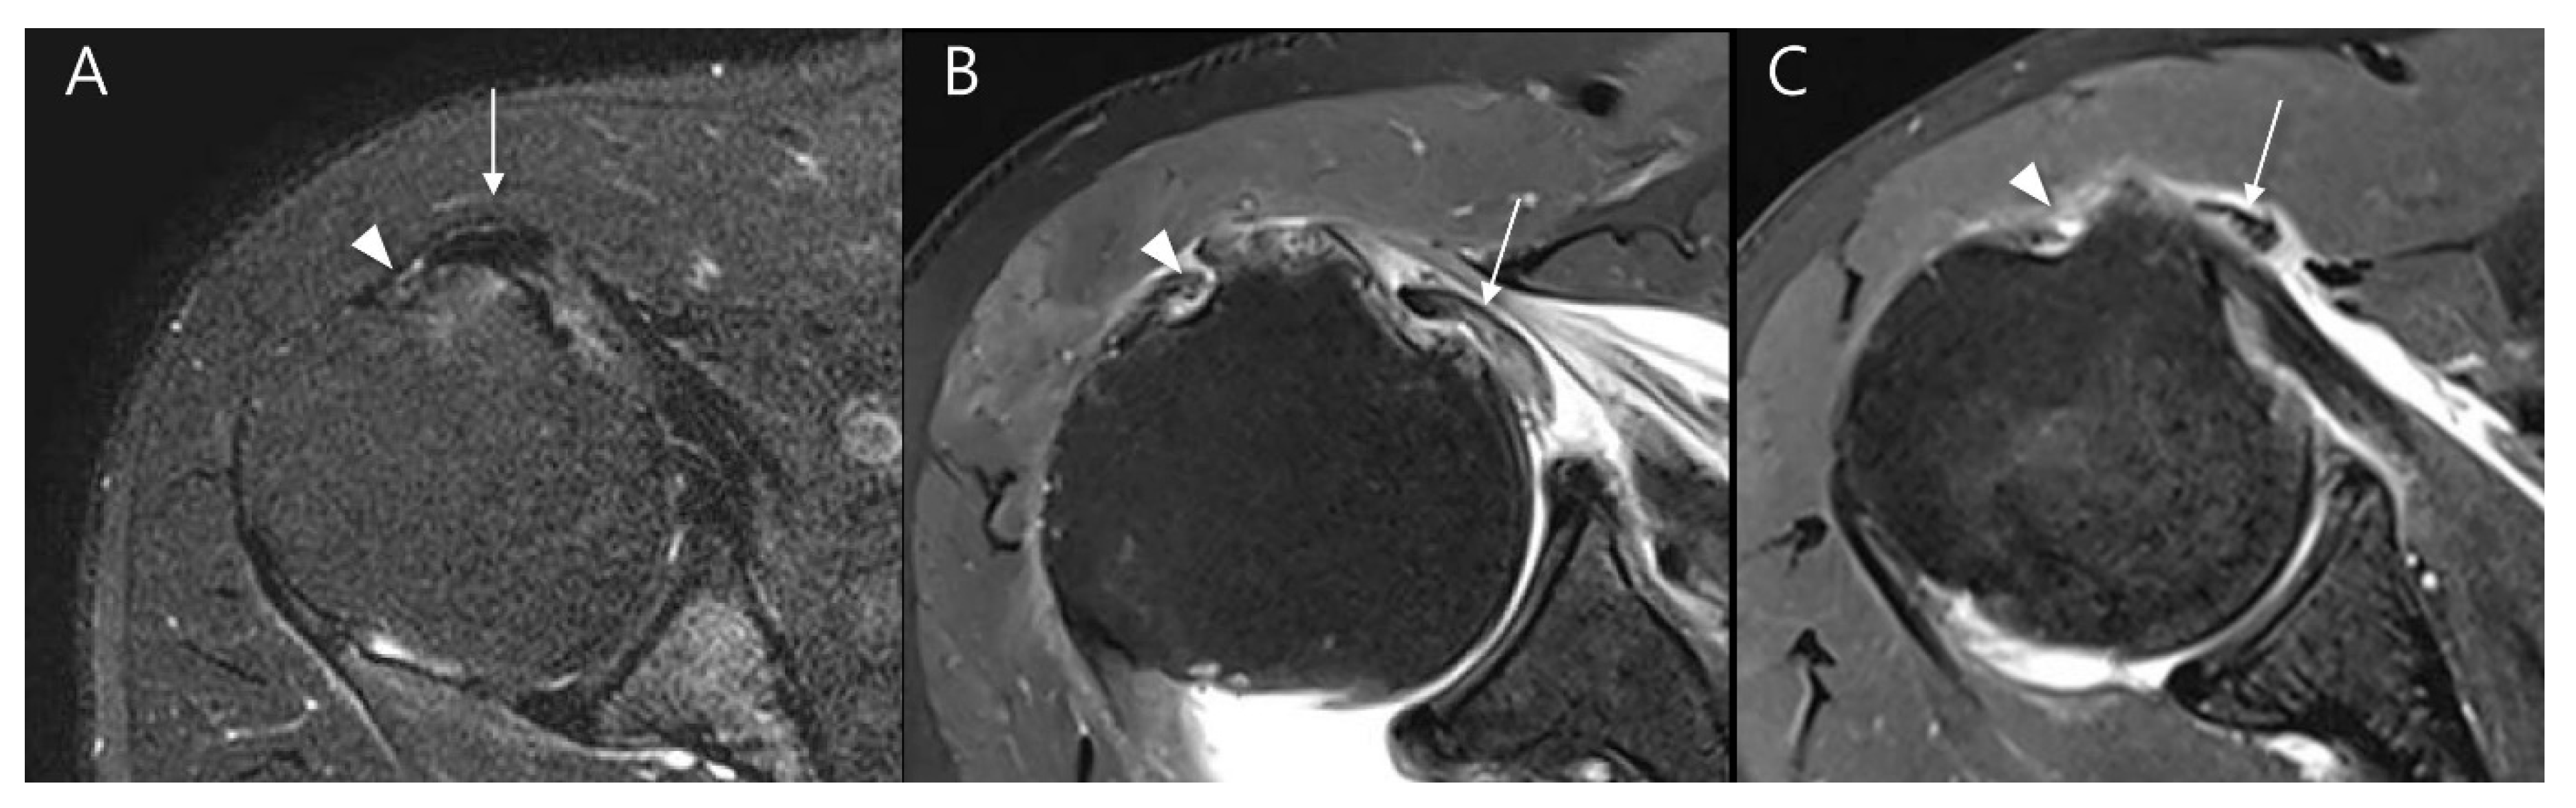

| Subscapularis muscle atrophy | <0.001 | κ = 1.000 (p < 0.001) | ||

| None to mild degrees (%) | 110 (99.1) | 21 (65.6) | ||

| Moderate to severe degrees (%) | 1 (0.9) | 11 (34.4) | ||

| Subscapularis muscle fatty infiltration | <0.001 | κ = 0.818 (p < 0.001) | ||

| None to some fatty streaks (grade 0 and 1, %) | 109 (98.2) | 25 (78.1) | ||

| Less or more than 50% of fat than muscle (grade 2 and 3, %) | 2 (1.8) | 7 (21.9) | ||

| Lesser tuberosity cyst (%) | 28 (25.2) | 15 (46.9) | 0.033 | κ = 1.000 (p < 0.001) |

| Long head biceps tendon pathologies | ||||

| Full thickness tear (%) | 4 (3.6) | 5 (15.6) | 0.040 | κ = 1.000 (p < 0.001) |

| Partial thickness tear (%) | 47 (43.9) | 25 (92.6) | <0.001 | κ = 0.981 (p < 0.001) |

| Tendinosis (%) | 76 (71.0) | 27 (100.0) | 0.003 | κ = 0.899 (p < 0.001) |

| Subluxation or dislocation (%) | 13 (12.1%) | 22 (81.5%) | <0.001 | κ = 0.853 (p < 0.001) |